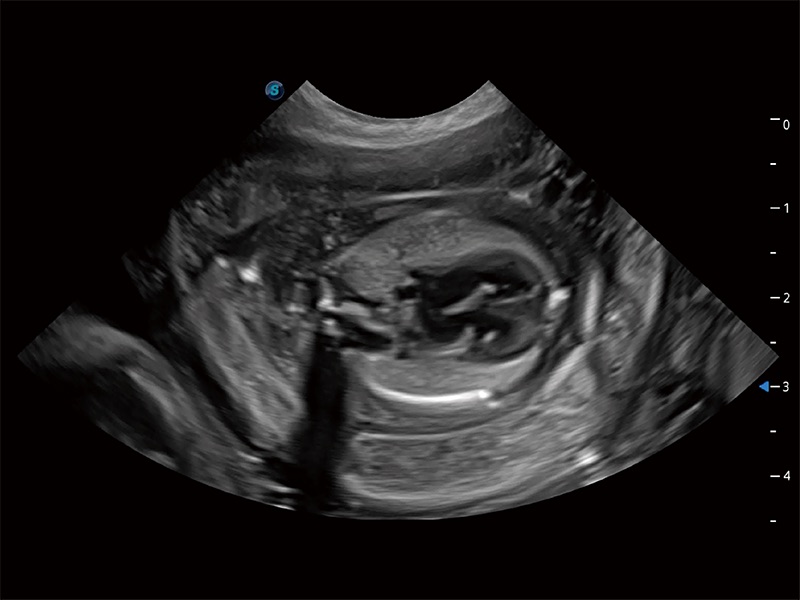

高性能和先進(jìn)的臨床應(yīng)用工具可以為動物醫(yī)生提供臨床信心。ProPet 80 搭載了先進(jìn)的腹部和淺表應(yīng)用工具,幫助醫(yī)生在日常臨床實(shí)踐中發(fā)揮前所未有的作用。

ProPet 80 專為動物醫(yī)生設(shè)計,對不同的動物體型和生理結(jié)構(gòu)作出了針對性的優(yōu)化。通過動物影像專用軟件,可滿足個性化的應(yīng)用需求,幫助動物醫(yī)生獲得更精確的診斷數(shù)據(jù)。

ProPet 80 全新的動物超聲智能軟件和豐富的探頭群,為動物醫(yī)生提供了高清晰度和精細(xì)分辨率的圖像,無論在寵物、馬科、畜牧還是實(shí)驗(yàn)室動物等應(yīng)用中都可以輕松應(yīng)對,為您的日常工作帶來滿意的體驗(yàn)。